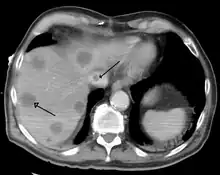

- El cáncer hepático primario generalmente se manifiesta comohepatocarcinoma y/o colangiocarcinoma; las formas más raras incluyen angiosarcoma y hemangiosarcoma hepáticos. (Muchos cánceres hepáticos son lesiones secundarias que han metastatizado de cánceres primarios en el tracto gastrointestinal y otros órganos, como los riñones o los pulmones.)[14]

Una hepatopatía previa no diagnosticada se puede detectar tras la autopsia. Abajo se muestran imágenes de la patología:

Metástasis hepáticas